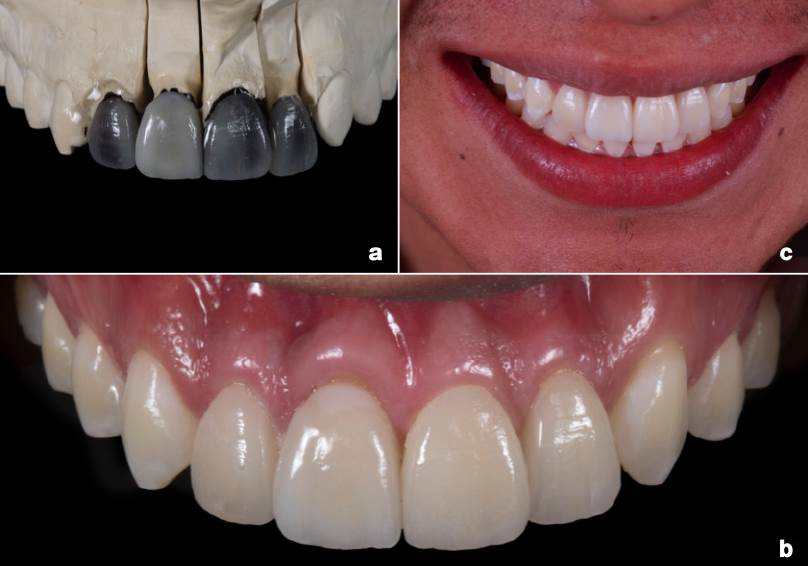

Se realizó la preparación de la corona del diente 11 con fresa de carburo y se realizó la hibridación dentinaria con técnica Resin Coatingn12 (ClearfilTM SE Bond Kit + ClearfilTM AP-X Esthetics Flow, Kuraray Noritake Dental Inc., Okayama, Japón) complementando las preparaciones para carillas de disilicato de litio (IPS e.max Press, Ivoclar Vivadent AG, Liechtenstein) de los dientes anteriores 12, 21 y 22, tomando color de núcleos (Figura 3.D) para la realización de las restauraciones (Figura 4.A). Para la cementación se realizó la reactivación del Resin coating con Óxido de Aluminio (Al2O3) a 50µm a 3.5 bar durante 5s con una distancia de 10mm13. Finalmente, se realizó la cementación con cemento largo plazo dual self-etch libre de aminas14 (PanaviaTM V5 Clear, Kuraray Noritake Dental Inc., Okayama, Japón) para garantizar la estabilidad de color transparente y compensar la atenuación del disilicato de litio en la pérdida de energía lumínica (Figura 4B-C).